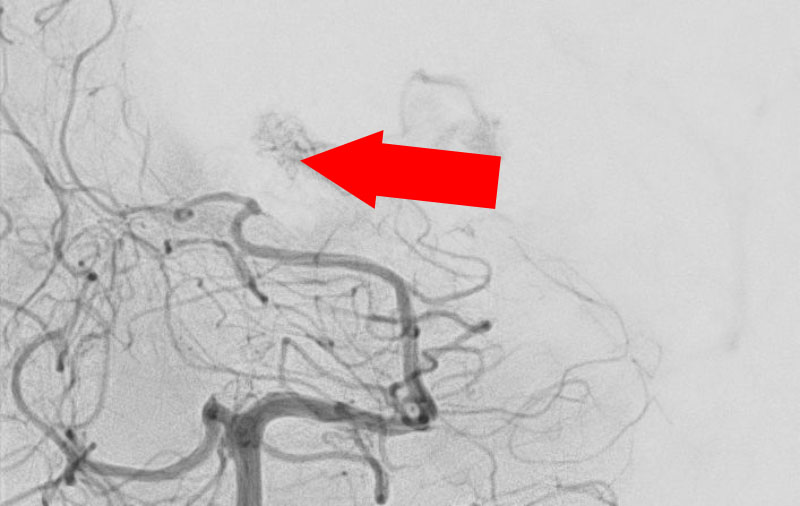

No.1583 手術前

No.1583 手術中

No.1583 手術後